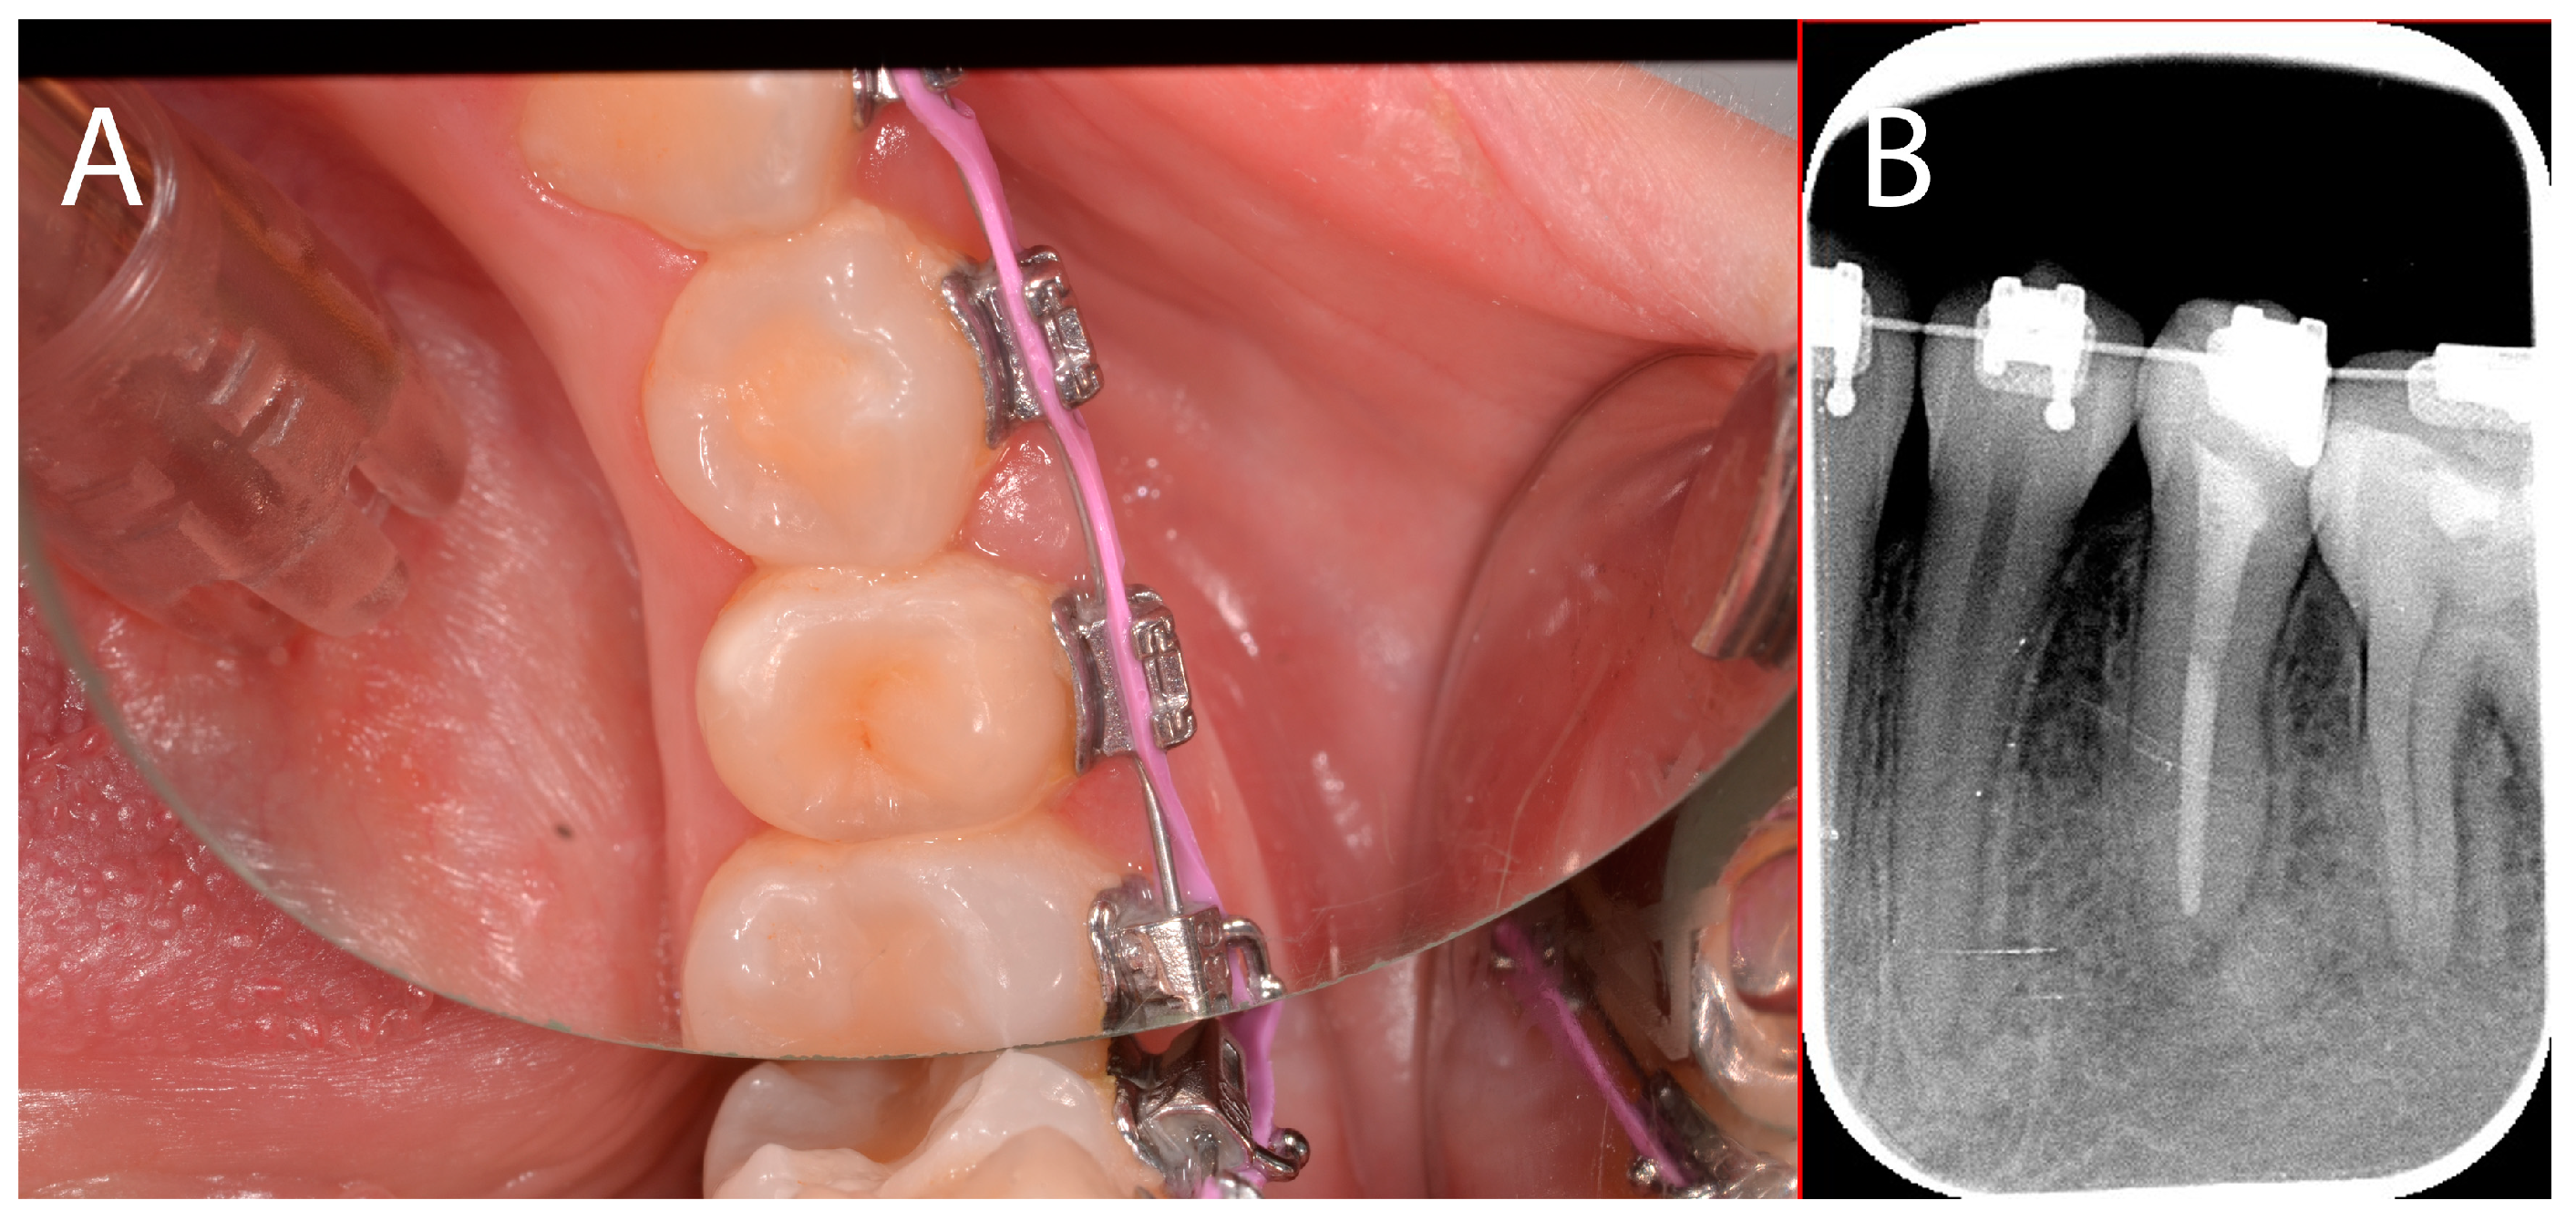

2.3. Case Presentation #2

2.3.1. Anamnesis, Physical Examination

2.3.2. Treatment